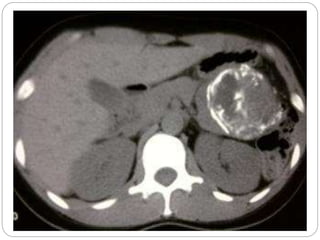

• #9 Hemorrhagic tumor of the head of the pancreas without involvement of the Wirsung.

• #10 Encapsulated solid hemorrhagic tumor.

• #11 The tumor can present as a well-demarcated, hemorrhagic cystic mass mimicking a pseudocyst.